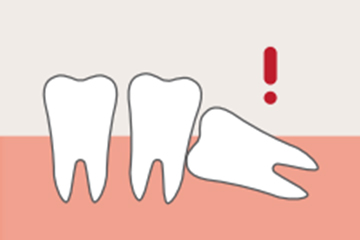

흔히 ‘사랑니’라고 부르는 이 치아의 치의학 명칭은 ‘제3대구치’ 입니다.

세번째로 나는 큰 어금니라는 뜻입니다. 17세~25세 턱뼈의 성장이 완료 된 시점에 새로나는 어금니로 가장 안쪽에 좁은 상태로 나오게 됩니다.

사랑니의 형태는 누워있거나 일부만 보이거나, 혹은 아예 숨어있는 등 여러 형태로, 형태에 따라 발치르 할지 발치 없이 유지관리 할지를 결정하게 됩니다.

많은 치아들 중 턱뼈가 모두 성장한 이후에 가장 늦게 나기 때문에 치열의 가장 안쪽 좁은 곳을 뚫고 나옵니다.

좁은 곳에 나기 때문에 누운 상태로 나거나, 턱뼈를 자극하는 각도로 뿌리를 내리거나, 잇몸에 숨겨진 상태로 나는 등 비정상적으로 자리를 잡게 되기 쉽습니다. 그리고 사랑니는 치열 안쪽 깊숙이 자리해 있기 때문에 칫솔질이 닿기 힘듭니다.

칫솔질이 잘 닿지 않는 사랑니와 옆 치간에는 음식물 등 세균이 잔류하게 됩니다. 잔류 음식물이나 세균 등은 결국 치태가 되고 치태는 치석이 되어 사랑니뿐만 아니라 사랑니 근처 치아에까지 충치와 치주 질환을 유발하게 됩니다.

사랑니가 옆으로 누워서 난 경우

사랑니 잇몸에 염증이 간헐적으로

생긴 경우

음식물이 끼어 옆의 치아가

썩을 경우

칫솔이 닿지 않아 관리가

되지 않은 경우

잇몸 속에 숨어서 자란 경우

옆의 치아를 밀어 부정교합을

유발하는 경우